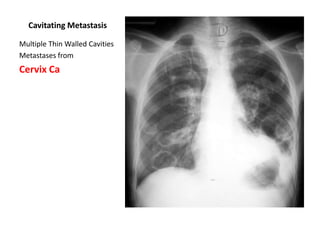

Cavitating Metastasis

Multiple Thin Walled Cavities

Metastases from

Cervix Ca